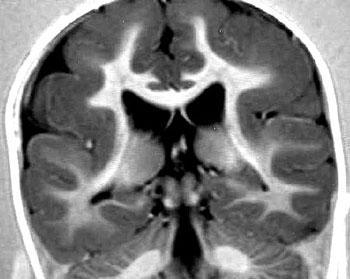

La superficie de un cerebro normal está formada por una serie compleja de pliegues y surcos. Los pliegues se denominan giros o circunvoluciones y los canales se denominan surcos. En niños que padecen de lisencefalia, las circunvoluciones normales están ausentes o se han formado solamente en parte, haciendo que la superficie del cerebro sea lisa. Los niños afectados suelen mostrar retraso psicomotor grave, retraso del desarrollo, convulsiones y espasticidad muscular o hipotonía.